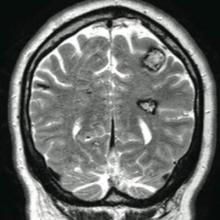

The patient’s medical history was remarkable for neurologic symptoms including adult-onset seizures at the age of 42 years. Recent magnetic resonance imaging of the head showed multiple areas of heterogeneous signal intensity with T2 hypointense rims consistent with cerebral cavernous malformations (CCMs) involving both cerebral hemispheres, the posterior cranial fossa, and the brainstem (Figure 5). Of note, the patient’s mother had been diagnosed with epilepsy in her 40s, but no other family history of a clinically or radiographically diagnosed neurologic disorder was reported.